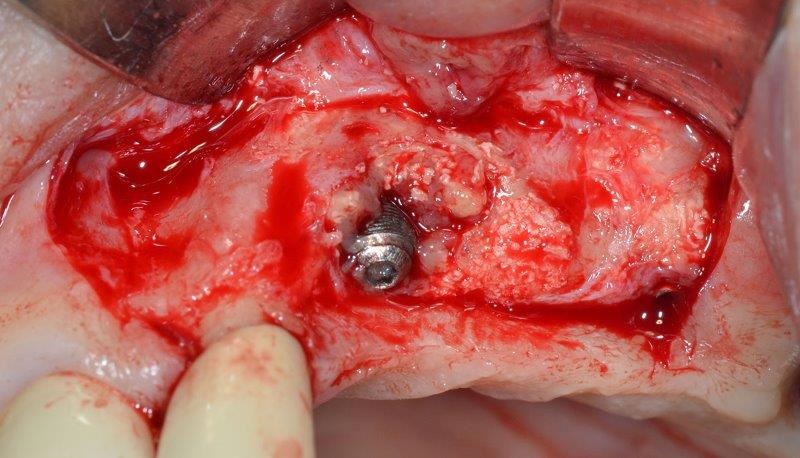

After flap elevation, a large peri-implant defect with the presence of nonintegrated biomaterial granules, perhaps remaining from a previous surgical procedure, was detected (Fig. 8). Accurate debridement of the granules embedded in reactive tissue was carried out by means of a dedicated ultrasonic tip (Fig. 9).

Horizontal bone thickness (HBT) and vertical bone defect (VBD) around the exposed part of the implant were measured at the baseline with a periodontal probe, then the cover screw was removed to decontaminate both outer and inner surface of the implant.

The ultrasonic cavitation device was placed onto the exposed part of the implant—there’s no need to create a tight seal between cavitation chamber and crestal bone—and the device was then activated (Fig. 10). A non-contact approach (without the metal tip contacting the implant) is advisable to avoid damaging the implant.